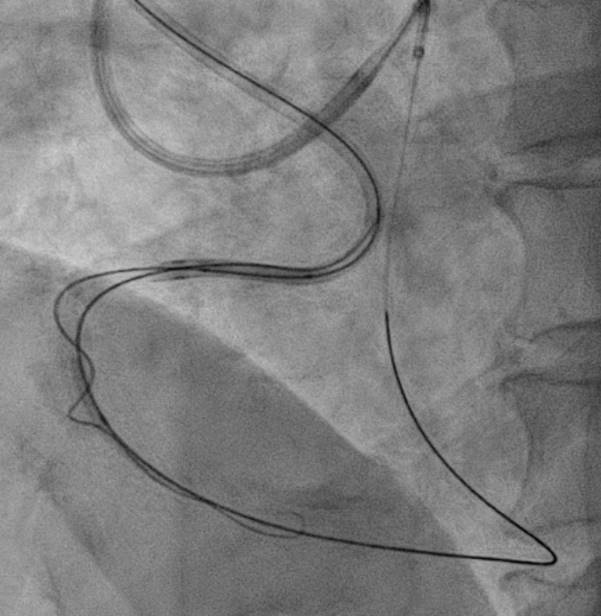

The strategy we plan was antegrade preparation and early retrogradly approach, due to challenging antegrade approach and also distal bifurcation1.XTA+Caravel microcatheter for antegrade preparation, failed advancement in mRCA2.retrograde with suoh03, but could not advance caravel and cosair pro microcatheters through septal channel3.extension catheter use, and balloon dilation for septal channel with low pressure4.caravel could enter dRCA, distal injection5.retrograde wire escalation for calcified CTO: Gaia2, Gaia3, Conquest pro6.kissing wire technique within dRCA7.both side MC could not pass the CTO, despite both side extension catheter use(img: step01)8.intracoronary tip-in, with retrograde wire anchored within AL1(img: step02)9.still failed advancing both side MC10.retrograde balloon dilation, sequentially from distal to middle RCA(img: step03)11.successful antegrade wiring to PL12.lesion preparation and drug-eluting stent placement13.good final angiography results

For this complex CTO case, we applied the following methods for a successful PCI:1. better support by using AL and EBU guiding catheters, both side extension catheters and microcatheters2. switching microcatheters3. septal channel dilation for microcatheter advancement4. tip-in technique, and then antegrade balloon anchor 5. retrograde balloon dilation when both side microcatheters could not pass the CTO lesion and failed by antegrade balloon dilation